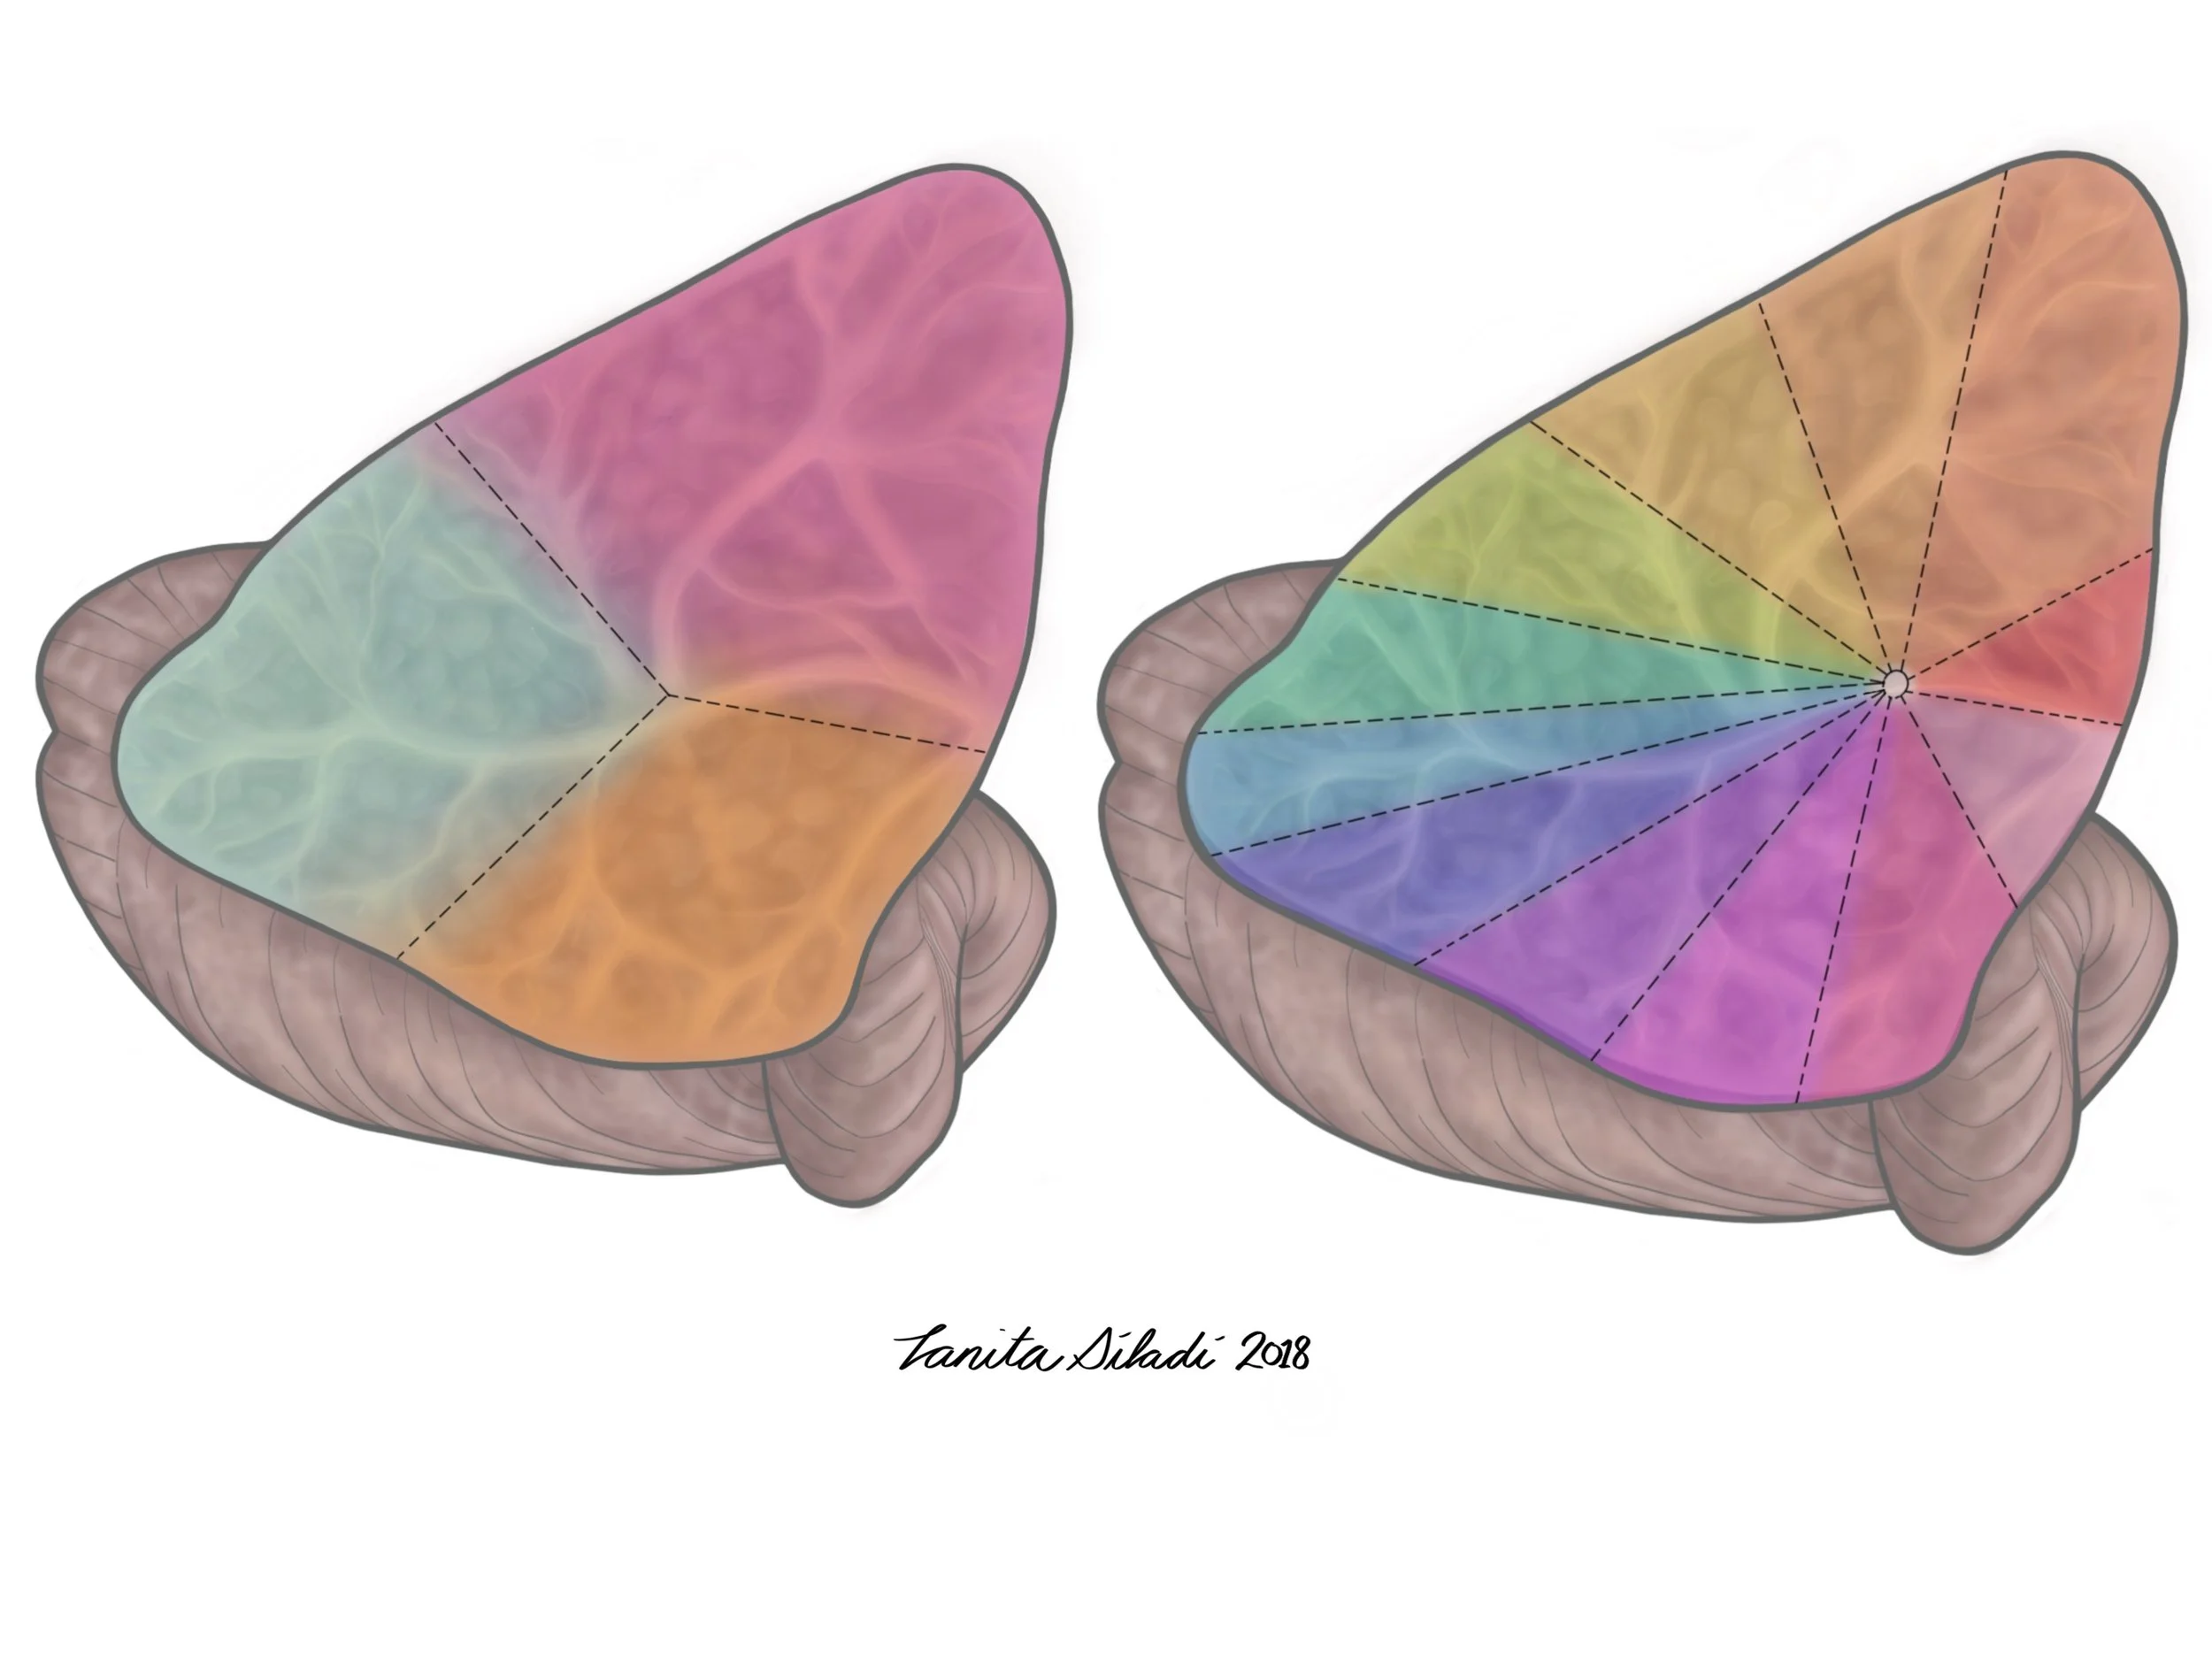

Dissertation illustration: Hurtubise, J. Behavioural effects of concussion history and their underlying neural mechanisms in elite and non-elite athletes. (July 2018)

Dissertation illustration: Hurtubise, J. Behavioural effects of concussion history and their underlying neural mechanisms in elite and non-elite athletes. (July 2018)